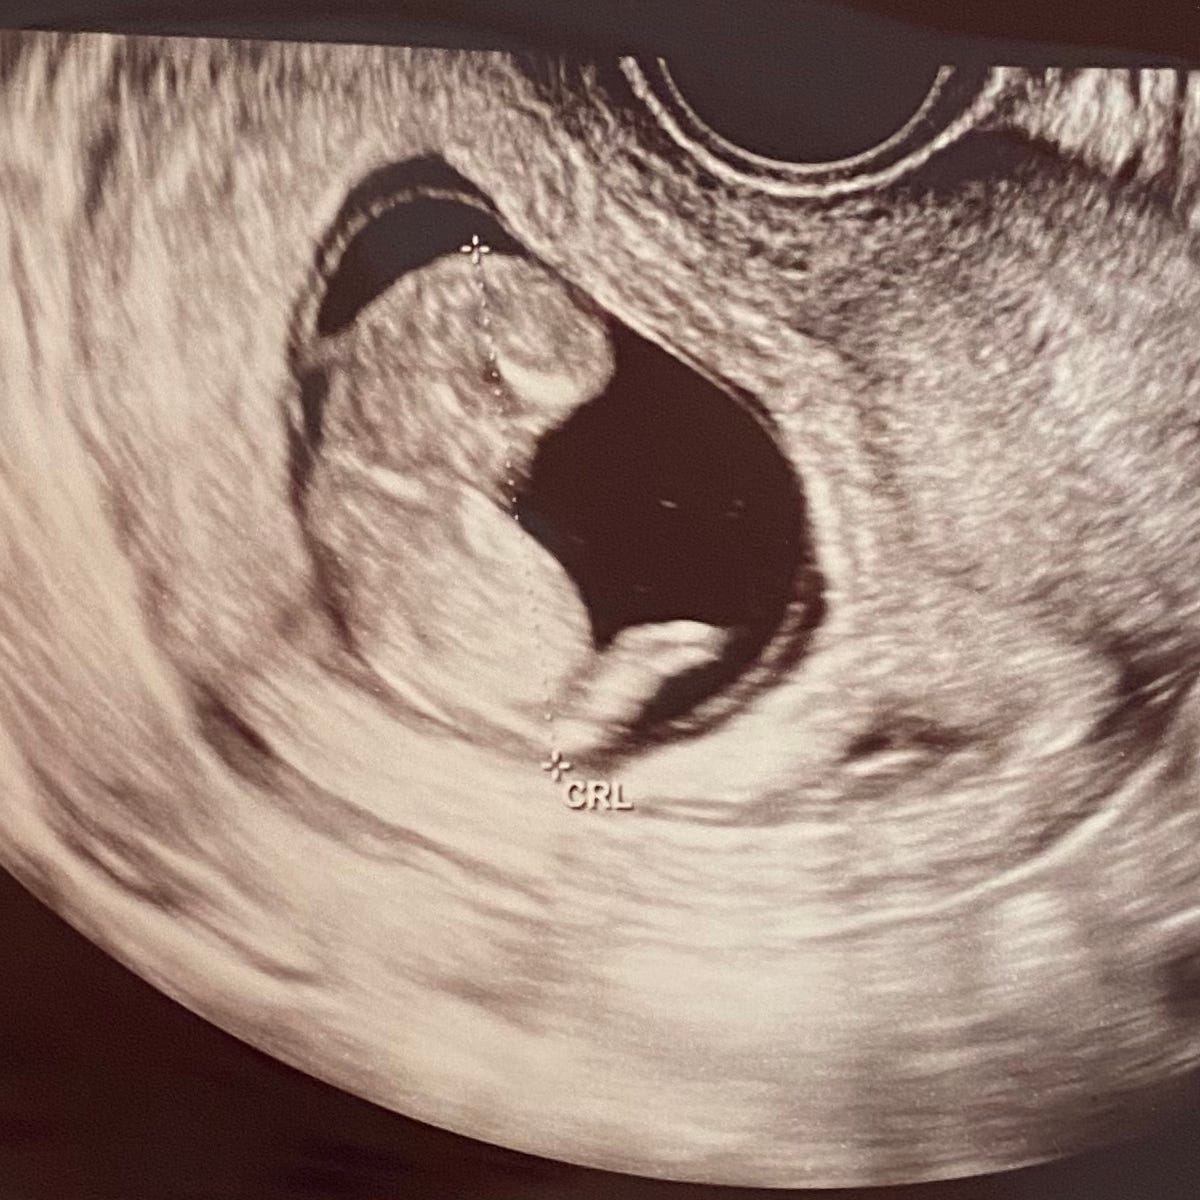

It’s not that the good outweighed the bad; it’s that the good was the bad, and all of it was just stuffed inside me haphazardly like a trash bag of old clothes for Goodwill. I’m here in spite of my eyes and because of my eyes—all at once. If I made it this far on this sloppy mix of genes, they couldn’t be that bad. Plus our baby would get 50% of Robin’s, which I personally think are pretty amazing. So we took the third path, one the retina guy hadn’t mentioned. We made a baby.

An hour after our daughter was born, a nurse pricked her heel to test her blood. The next morning, while we were still in the sleep-deprived bliss-haze of new parenthood, a pediatrician solemnly informed us that our daughter had inherited two mutated ABCA4 alleles. She had the genes for Stargardt’s.